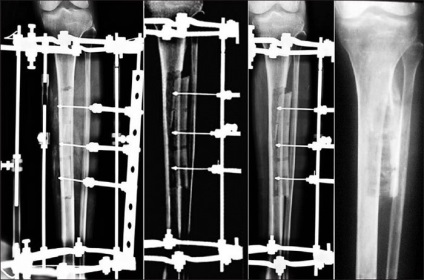

Se întinde oasele (formarea de os)

Se întinde oasele (formarea de os)

Femeile poarta tocuri sa arate mai inalt, sau sunt în mâinile Chihuahua pentru contrast. aparate Dr. Elizarov că el a creat în 1955, nu numai că va ajuta la creșterea fragmentului de os pentru uz cosmetic, dar, de asemenea, pentru a ajuta cu fuziunea fracturilor osoase sunt foarte grave. Acesta este un cadru metalic care deține osul deteriorat și permite organismului de a construi piesele lipsă. Dispozitivul poate fi reinstalat, dacă este necesar, atâta timp cât osul este ridicat lungimea necesară. Acesta este utilizat pentru corectarea defectelor congenitale ale scheletului.